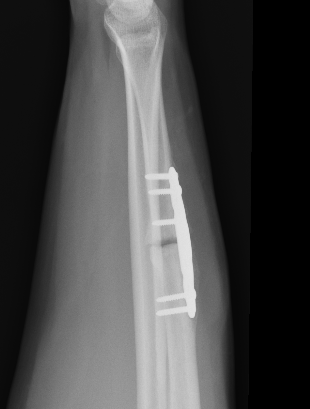

Operative management

Indications

Acute fractures

- > 50% displacement

- > 10 degrees angulation

Compression plating